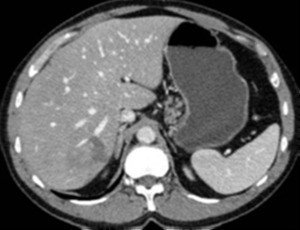

Abses diaqnozunu dəqiqləşdirmək üçün klinik əlmətlərlə yanaşı görüntüləmə və laborator müayinələr aparılmalıdır. Yerli və ümumi sepsis əlamətləri ilə yanaşı USM və ya tomoqrafiyada qaraciyərdə abses boşluğun görünməsi diaqnozu dəqiqləşdirir. Absesdə qaztörədən bakteriyalar olduqda və ya bağırsağa açılarsa içərisində qaz görünür (25%).

Diaqnostik əlamətləri:

• Sistlərdən fərqli olaraq abseslərin sərhədi kəskin olmur, möhtəviyyatının sıxlığı yüksək, hətta nekrotik toxumalar olarsa, heterogen görünür.